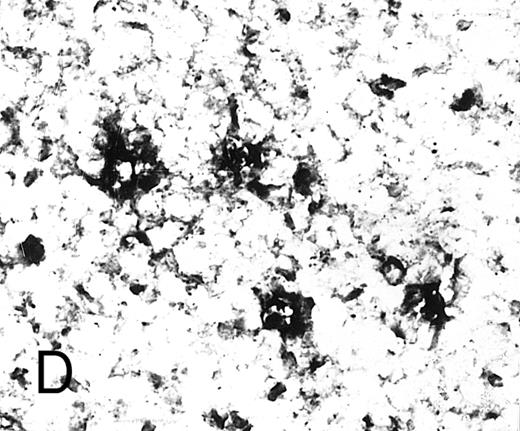

Expression of TGF-β and TGF-β receptor II in tonsillar lymphoid follicle. (A) Immunostain of TGF-β. There is the reticular and dotted positive stain in the apical and basal light zones but not the other follicular zones. MZ, mantle zone; LZ, light zone; DZ, dark zone. Counterstained with methyl green. Original magnification × 132. (B) Immunostain of TGF-βR II. There is the reticular expression in the apical light zone. OZ, outer zone; ALZ, apical light zone; BLZ, basal light zone; DZ, dark zone. Counterstained with methyl green. Original magnification × 100. (C) Immunocytochemical single staining (red color) of TGF-β on an isolated FDC. Original magnification × 1,280. (D) Double staining of TGF-β and R4/23 on the same FDC. There is a positive signal in the cytoplasm of FDC (brown). Counterstained with hematoxylin. Original magnification × 1,280. (E) In situ hybridization of TGF-β cDNA in the ALZ. Dendritic-shaped cells heavily labeled (arrows). Scattered lymphocytes are also stained (arrowheads). Uncounterstained. Original magnification × 860. (F) In situ hybridization of a TGF-βR II oligonucleotide in the ALZ. Many dendritic-shaped cells are strongly positive. Uncounterstained. Original magnification × 400.

Immunohistochemically, the ALZ but not the other follicular zones was positive in the reticular meshwork and dotted patterns for TGF-β and TGF-βR II (Tables 3 and 4 and Fig 1A and B). Immunocytochemically, FDCs isolated with MACS were single-positive for TGF-β in their cytoplasm (Fig 1C) and double-positive for TGF-β and R4/23 (Fig 1D). Less frequently, lymphocytes isolated with MACS were positive for TGF-β (<1%). In situ hybridization using a cDNA probe for TGF-β showed the reticular and dotted patterns only in the ALZ labeling cells such as dendritic-shaped cells and lymphocytes and the scattered pattern labeling vascular walls within the whole LF (Table 5 and Fig 1E). In situ hybridization using an oligonucleotide probe for TGF-βRII showed only the reticular pattern in the ALZ labeling dendritic-shaped cells (Fig 1F). Vascular walls within the whole LF were also reacted. Follicular lymphocytes were negative. RT-PCR of samples obtained from the whole tonsillar sample as well as the GC and EGC showed a single-positive band of TGF-β (161 bp; Table 6 and Fig 2A).